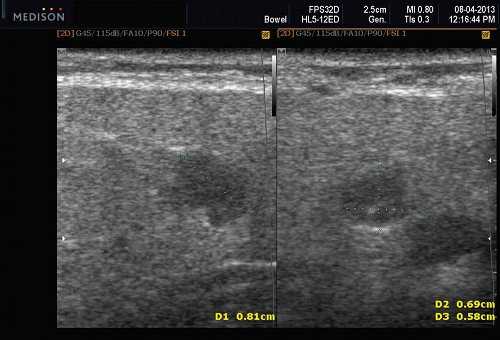

При проведении ультразвукового исследования слюнных желез специалист оценивает их размер, структуру, форму и наличие патологических изменений. Высокая разрешающая способность ультразвукового аппарата позволяет выявить даже минимальные изменения, которые могут быть связаны с развитием сиалоаденита.

Ультразвуковая диагностика позволяет определить одно- или двусторонний характер поражения слюнных желез, а также выявить общие признаки воспалительных процессов. С помощью ультразвука можно также оценить степень воспаления, наличие кист, опухолей и других патологических образований, которые могут быть связаны с сиалоаденитом.

УЗИ позволяет выявить такие признаки сиалоаденита, как увеличение размеров желез, наличие опухолей, изменения в структуре тканей и нарушения в работе слюнных протоков. Этот метод также позволяет оценить характер и степень воспаления, а также эффективность лечения при последующем контроле.